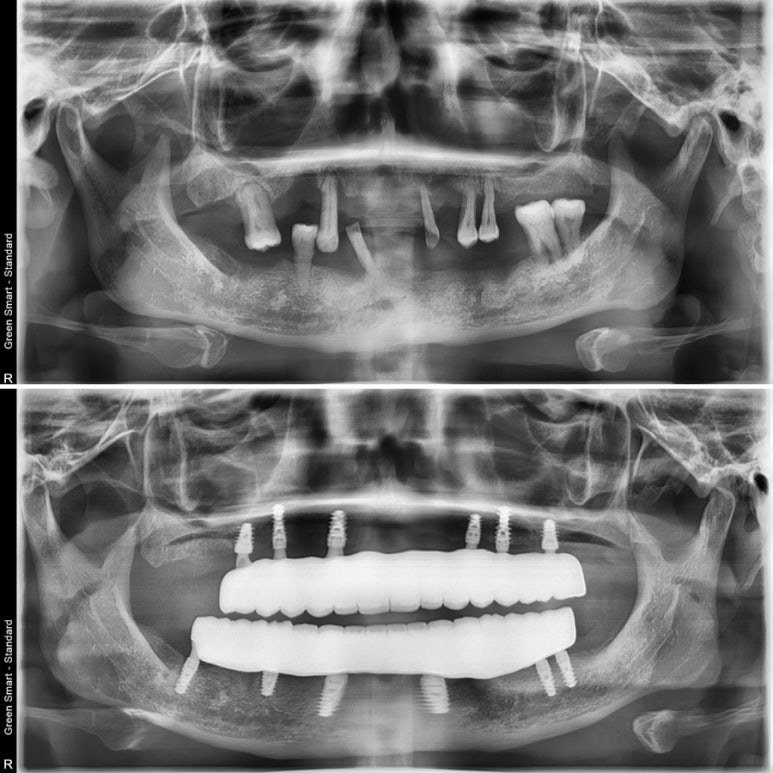

상하악 전체 임플란트를 위해 미국에서 찾아오신 환자분이셨어요.

식사도 발음도 너무 어려운 기존 상태에서 아몬드도 씹으실 수 있을 만큼 튼튼한 치아로 바뀌었답니다.

전체 임플란트는 임시치아가 시술 당일에 완성되기 때문에 임플란트 초기고정력이 매우 중요하답니다. 본원에서는 스위스 스트라우만 BLX 임플란트를 통해 강한 초기고정을 얻어 마무리 한 케이스 랍니다.

치아가 몇개 남지 않으신 상황이었고, 그나마 있는 치아들도 많이 흔들리시는 상황이었답니다.

자연스럽고 튼튼한 풀지르코니아 보철물이 완성되었어요.

엑스레이 전과 후 비교사진이랍니다.